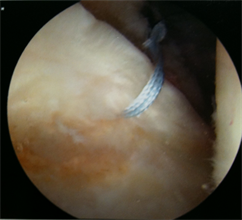

Labral repairs (see the stitch in the labrum in the picture on the right) are now commonly performed by hip arthroscopy surgeons, with Melbourne becoming a major hub for hip arthroscopy.